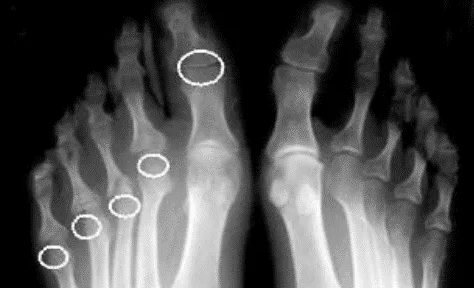

Периферический артрит клинически проявляется болью, припухлостью, ограничением подвижности суставов. Характерные признаки – артрит дистальных межфаланговых суставов кистей/стоп и «редискообразная» деформация, осевой артрит (одновременное поражение трех суставов одного пальца), дактилит и «сосискообразная» деформация пальцев кистей и стоп.

Рисунок 12. Рентгенограмма стоп при псориатическом артрите. Асимметричный эрозивный артрит с остеолизом ПлФС правой стопы и внесуставная эрозия 1-го межфалангового сустава

Рисунок 13. Рентгенограмма пяточных областей в боковой проекции при псориатическом артрите. Видны энтезофиты в области плантарной фасции, эрозия задней поверхности пяточного бугра (стрелки).

3Характерные рентгенологические изменения при псориатическом артрите: сужение суставной щели; костная ремодуляция (резорбция концевых фаланг, крупные эксцентрические эрозии, остеолиз – деформация «карандаш в стакане») и пролиферации (краевые костные разрастания, периоститы, энтезофиты и костные анкилозы), асимметричный двусторонний/односторонний сакроилиит, паравертебральные оссификаты и краевые синдесмофиты